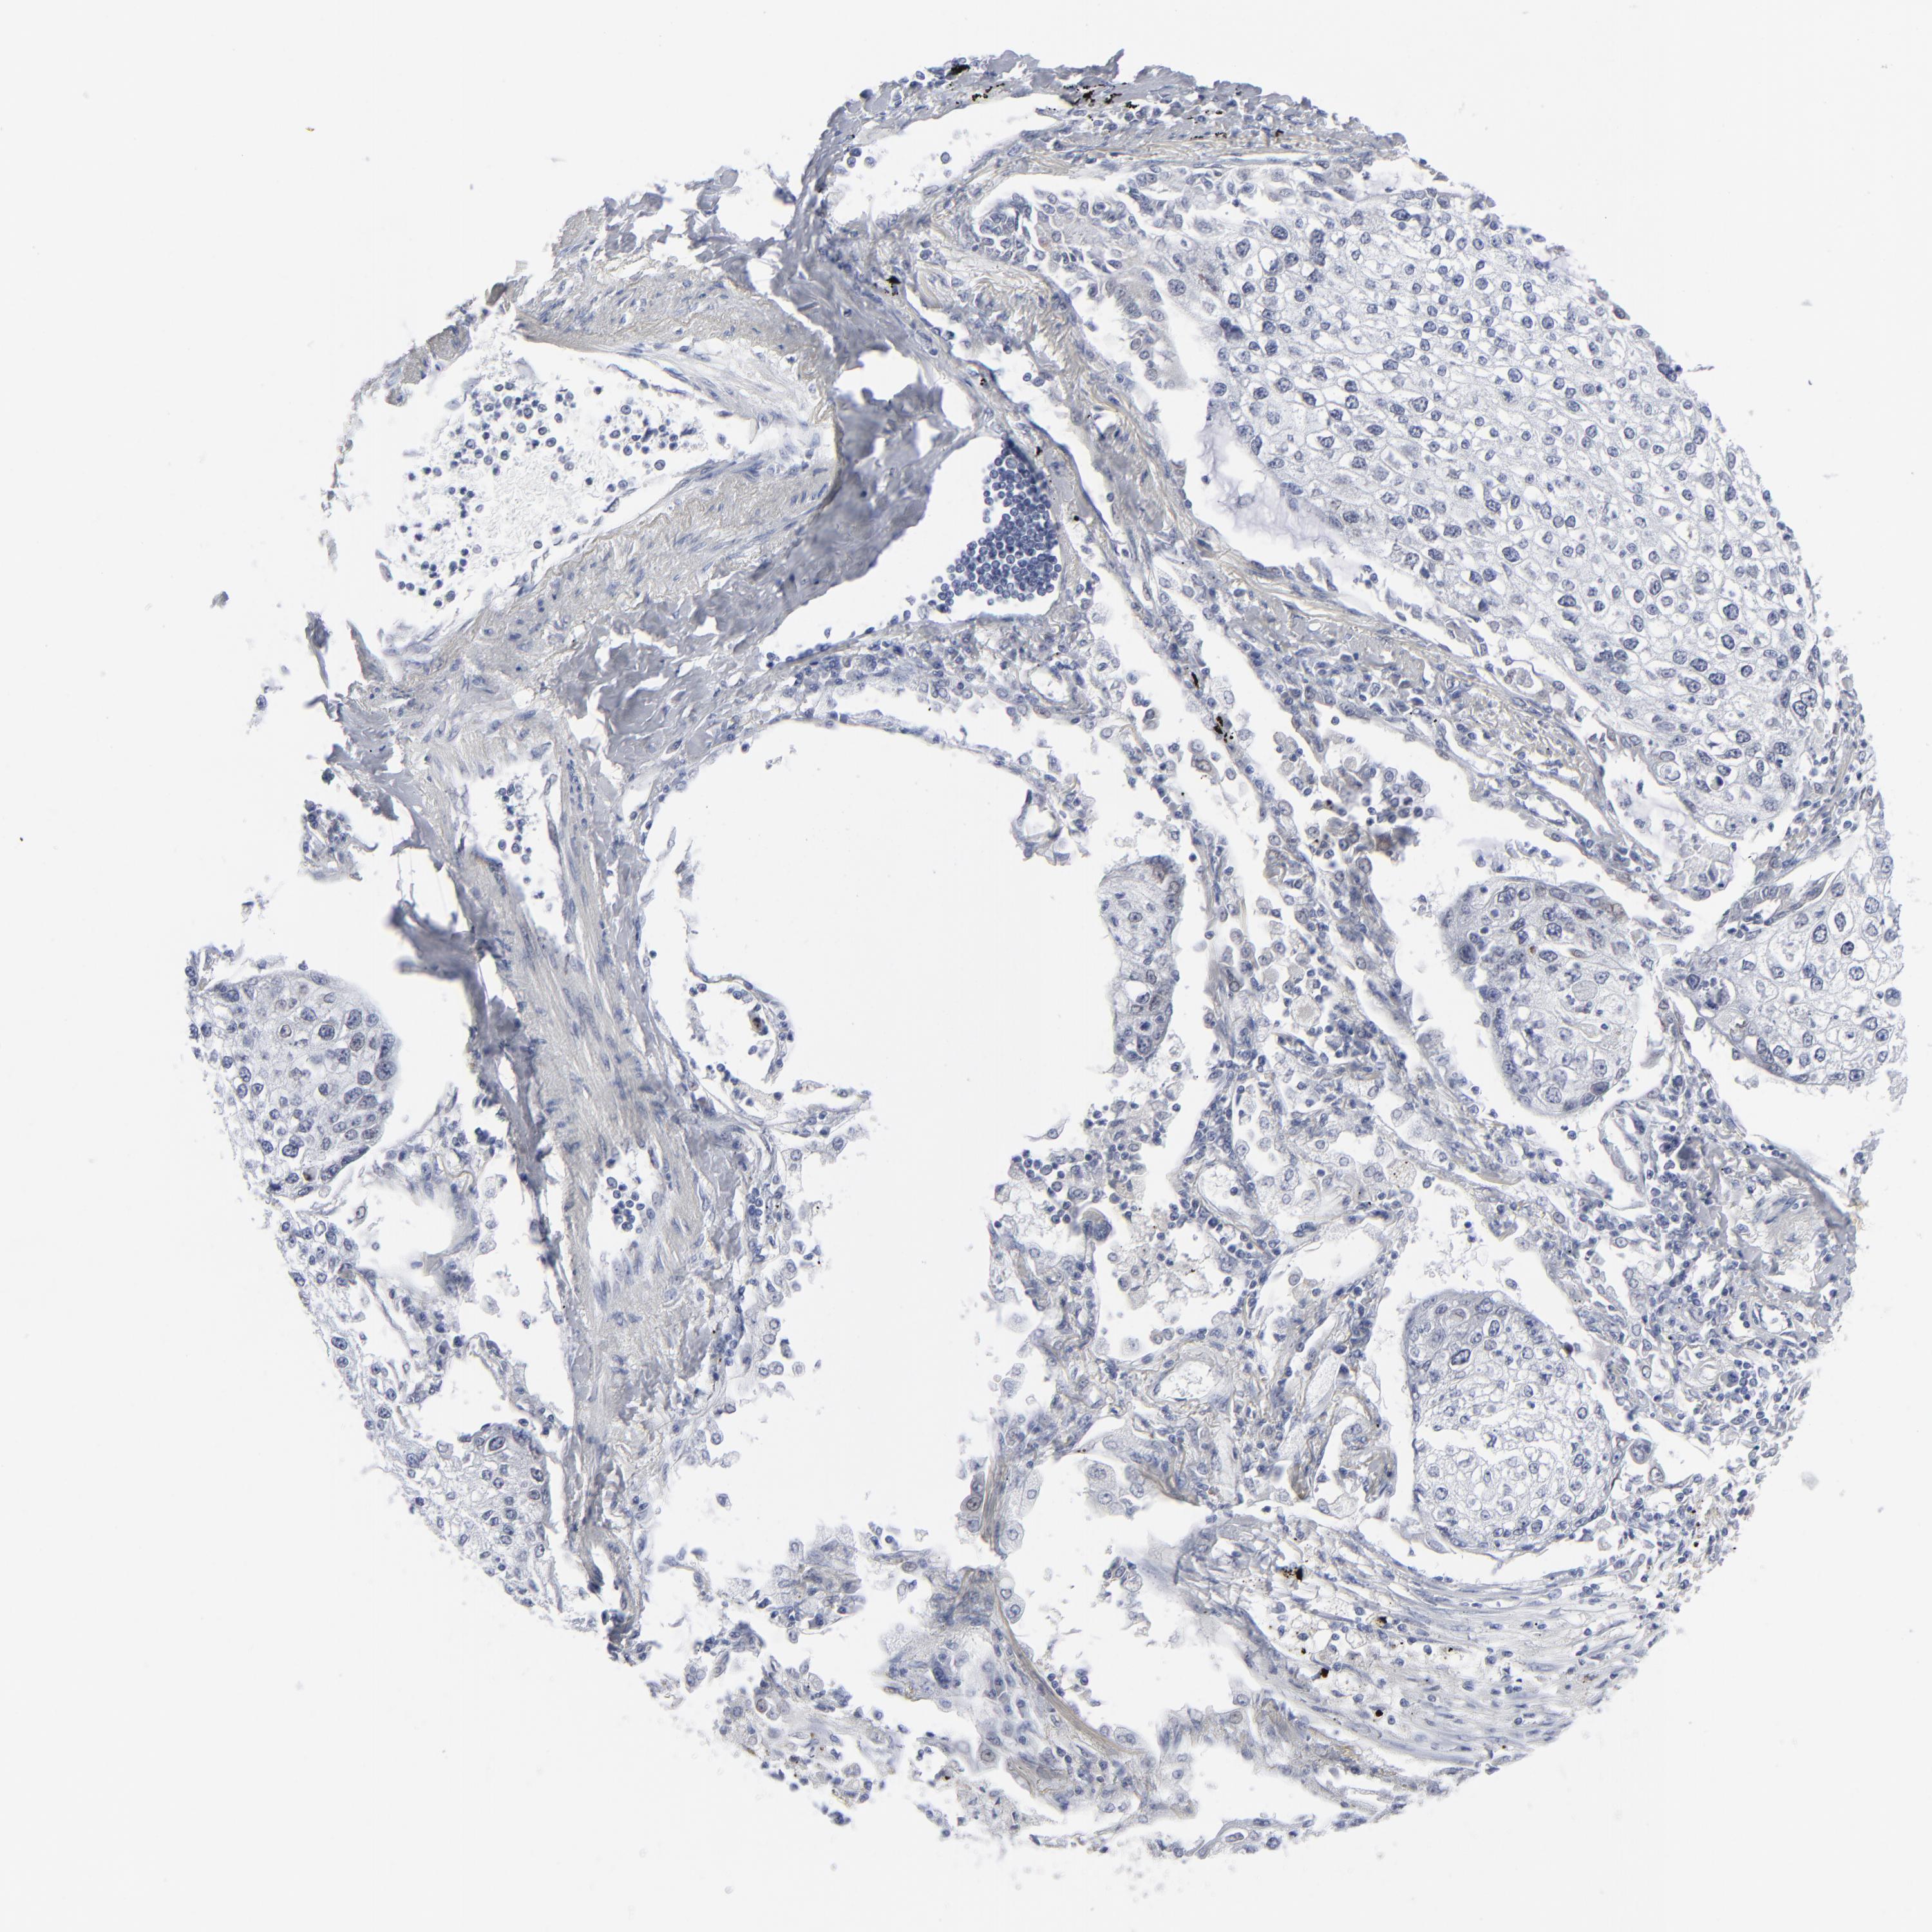

CANCER LUNG CANCER Show tissue menu